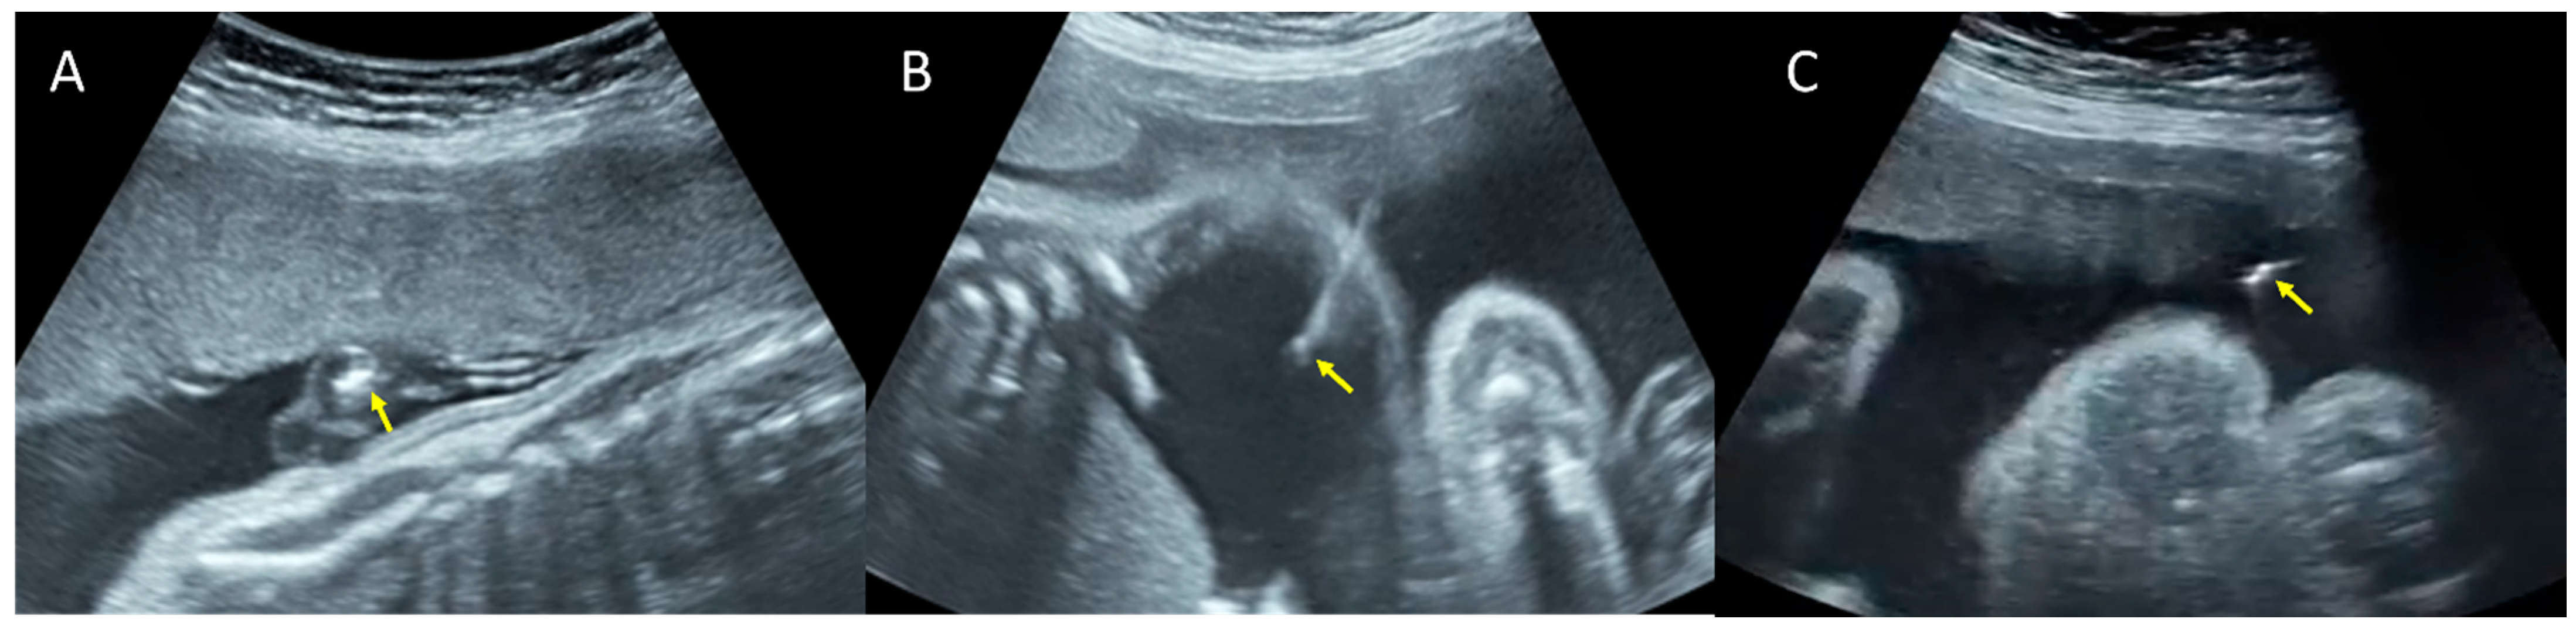

2. Case Report